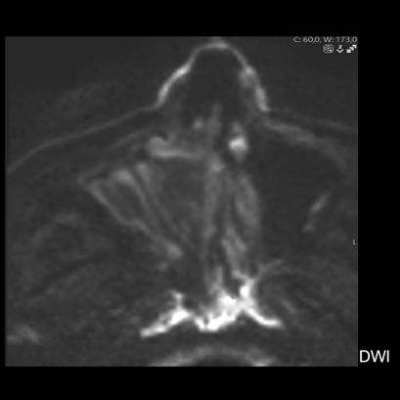

- B) BT incelemesinde maksiller sinüsün duvarları özellikle lateralde daha belirgin olmak üzere reaksiyonel kalınlaştığı izleniyor (oklar). DWI ve ADC haritasında lezyonda belirgin bir kısıtlılık görülmemektedir (oklar).

- MR incelemesinde sinonazal inverted papilloma tipik olarak T2 ve post-kontrast T1 serilerde ‘convoluted’ serebriform paternde heterojen sinyal ve kontrastlanma gösteren, pedinküler orijininde daha belirgin perfüzyon artışı sergileyen, genellikle difüzyon kısıtlaması izlenmeyen ve komşu sinüs duvarlarında ekspansiyona bağlı remodelinge yol açabilen benign ancak lokal agresif karakterde bir yumuşak doku kitlesi olarak izlenir.